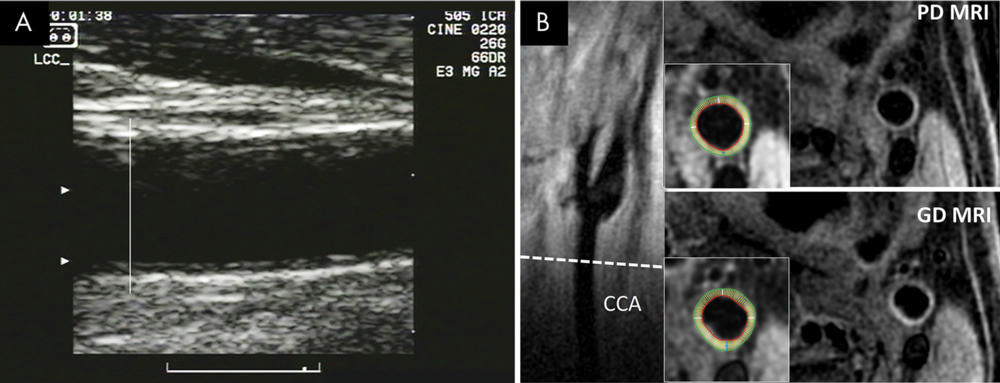

Vessel wall MRI is a promising, noninvasive technique that can image the entire carotid wall circumference, in contrast to ultrasound measurements of IMT that are usually based solely on views of the artery's far wall. MRI can also see all three layers of the artery, including the adventitia, the outermost layer not visible on IMT.

Figure 2. Images show common carotid artery (CCA) wall thickness assessment in a 62-year-old man by using, A, ultrasound and, B, MRI.